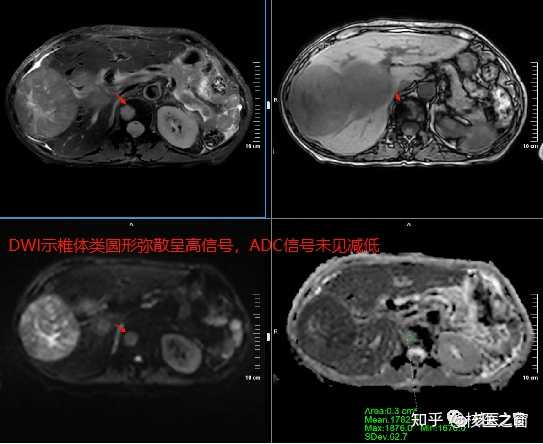

图6 PET/CT:椎体内见不规则异常密度,PET未显影

图7 与图6同层面,磁共振平扫+功能成像,清楚显示椎体病灶,特点与血管瘤一致

通过PET/CT结合磁共振平扫+增强+功能成像对比发现,腹主动脉周围多发淋巴结转移PET/CT与磁共振功能成像均能很好显示,PET/CT更直观展示了转移淋巴结的高亮信息,但胰腺前缘转移淋巴结在磁共振功能成像上显示清楚,在PET/CT上显影却浅淡,未表现出典型转移征象。

另外一个征象是椎体内低密度灶,在PET/CT上未见显影,但磁共振图像上病灶与其它正常区域分界清楚,特点呈典型血管瘤表现。

最后诊断:肝右叶巨块型肝癌并坏死,腹主动脉旁与胰腺前缘多发淋巴结转移;腰1椎体血管瘤。